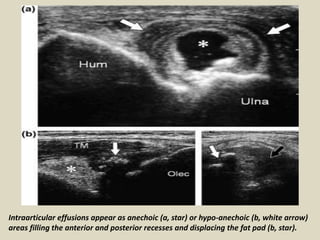

Intraarticular effusions appear as anechoic (a, star) or hypo-anechoic (b, white arrow)

areas filling the anterior and posterior recesses and displacing the fat pad (b, star).